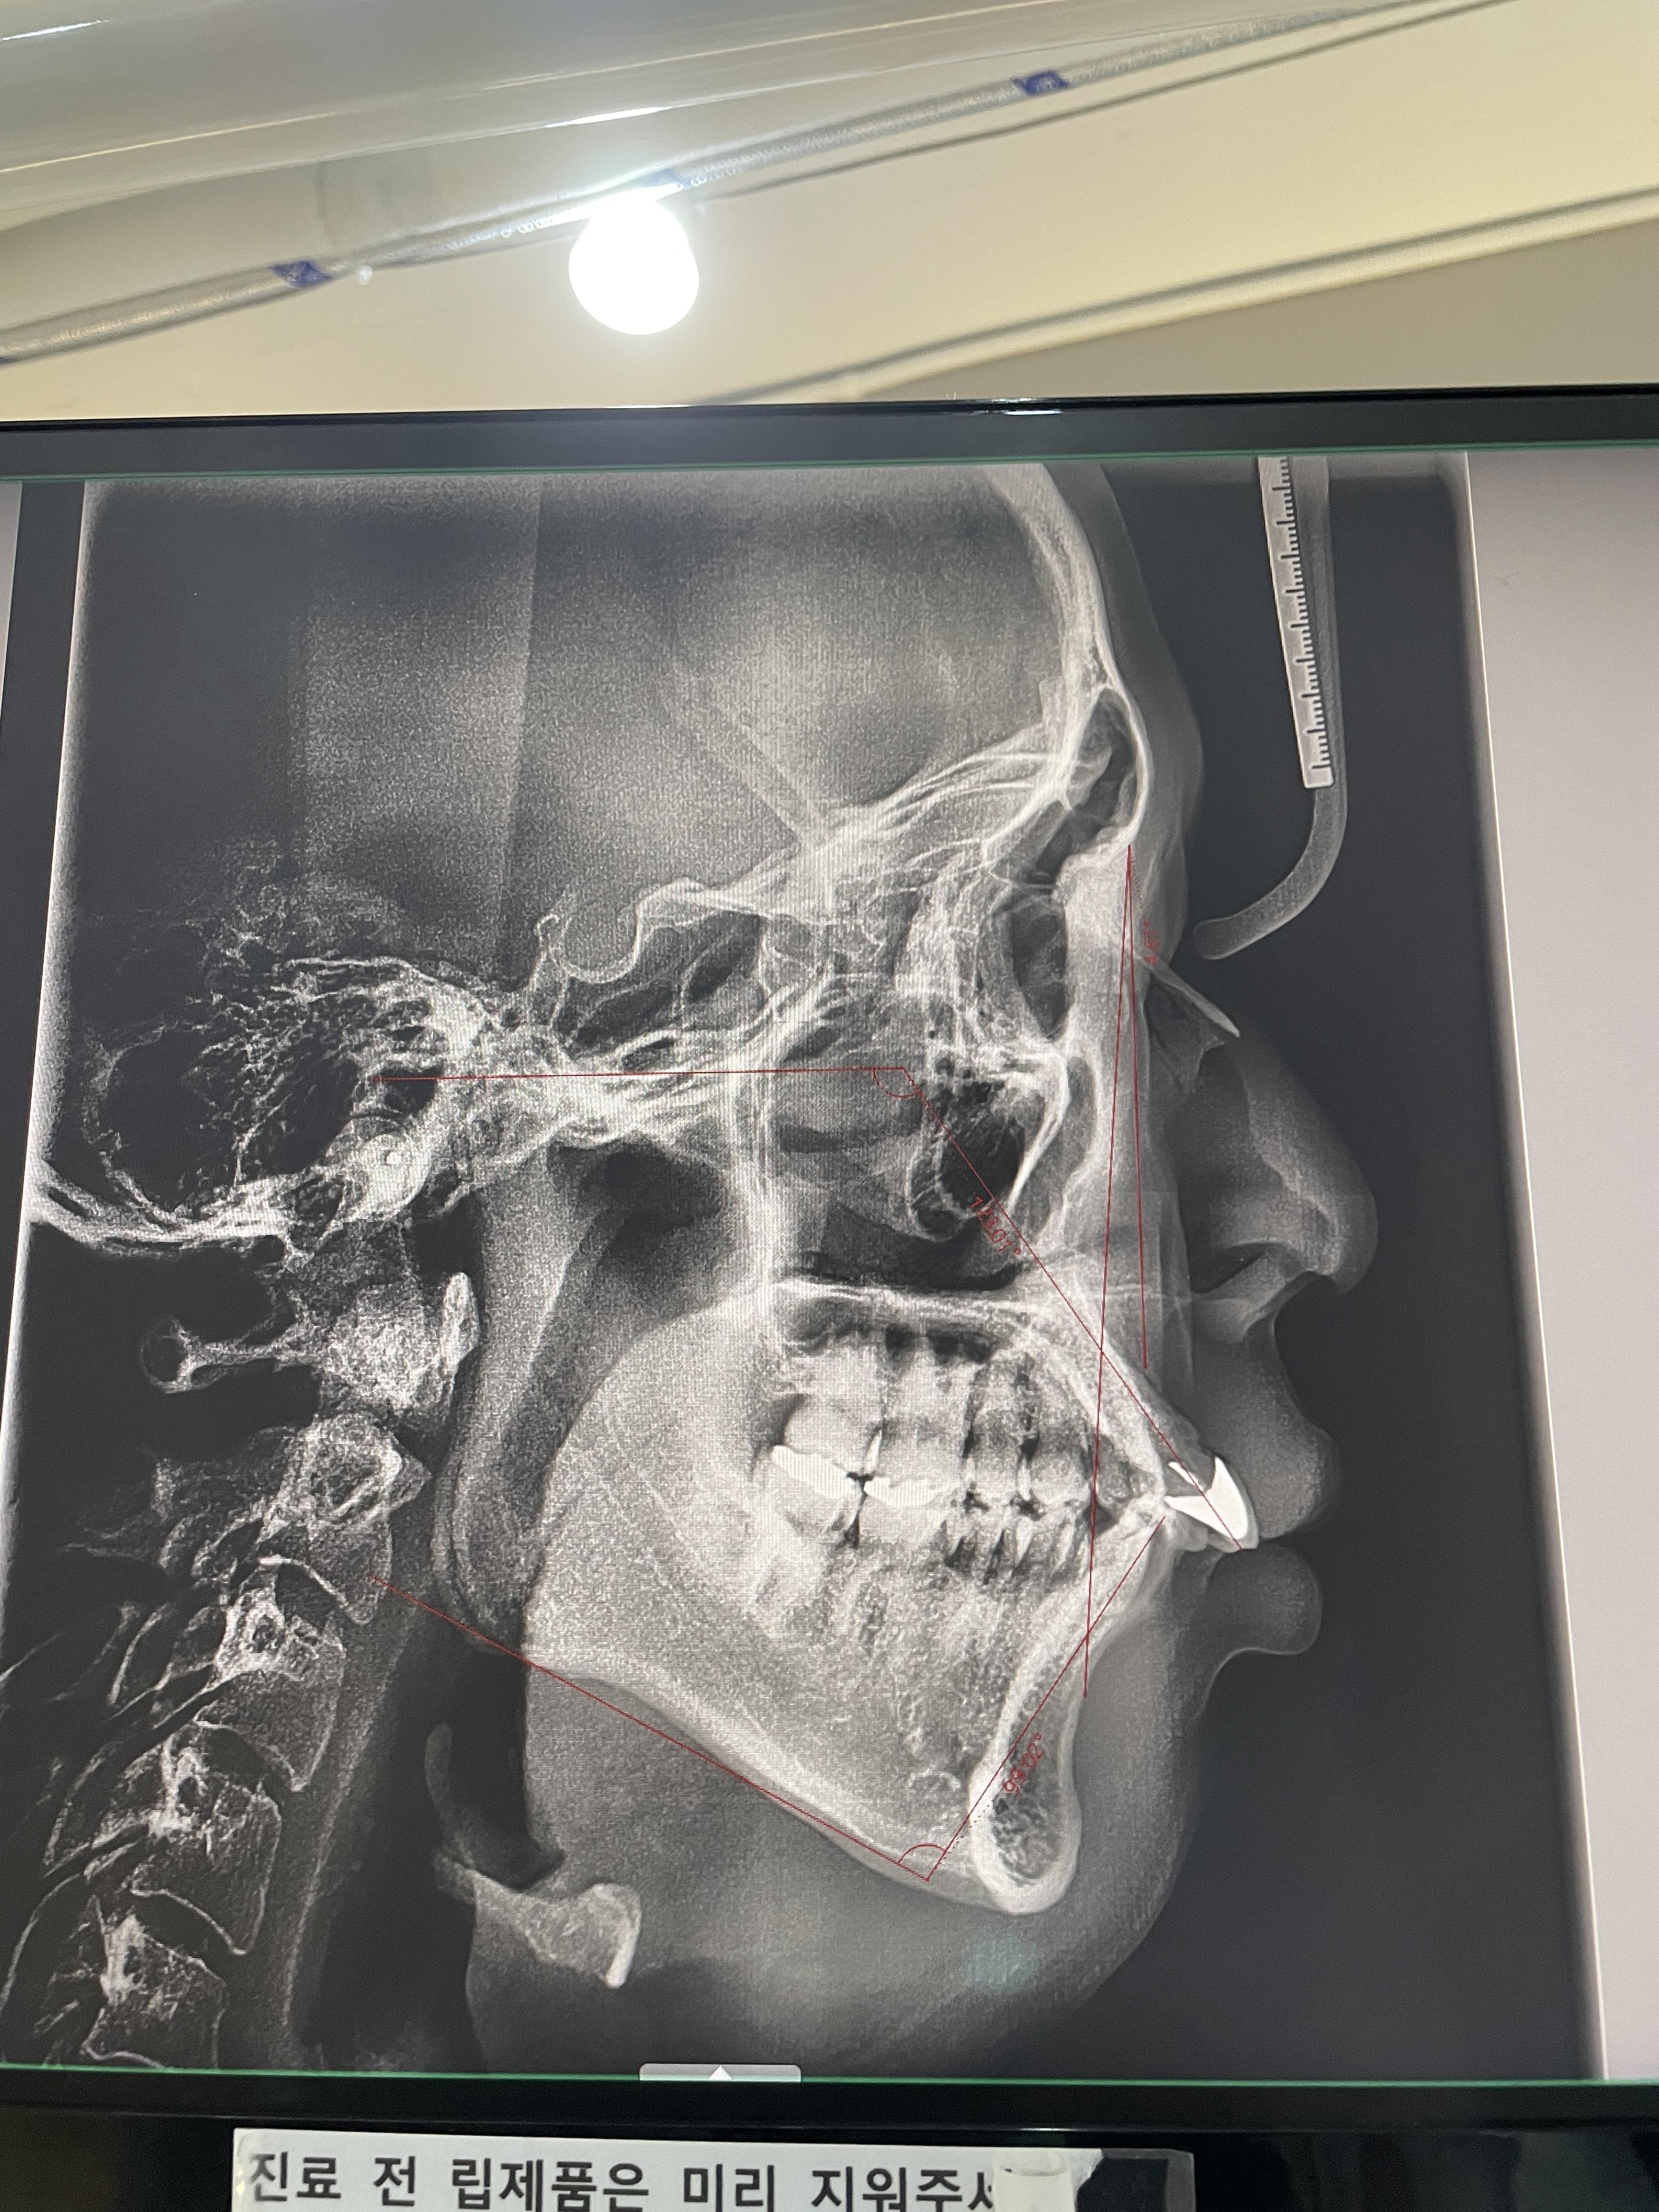

사진 상 하얀 부분은 고등학교 때 축구를 하다가 친구랑 충돌해서 빠졌던 앞니입니다. 그래서 다시 자리를 찾아 꽂아주었고, 치아 윗부분만 신경치료가 되어 있는 상태라고 해요. 처음 알게 된 사실인데, 치아는 원래 잇몸과 약간의 유격을 가지고 있다고 합니다. 그래서 치아를 움직여가며 교정이 가능한 것이라고 합니다. 교정이 끝난 뒤, 교정 보조물을 잘 껴주지 않으면 치아가 원래 상태로 돌아가는 것 역시 이렇게 유격이 있기 때문이라고 해요. 근데 이게 한 번 빠졌다가 다시 고정하기 위해 잇몸에 밀어넣으면, 그 유격이 사라지면서 치아와 잇몸이 붙어버린다고 해요. 그러면 어떻게 되느냐, 이가 움직이지 않는 상황이 되어버리는 것이지요. 돌출된 앞니를 집어넣고 싶던 제 계획이 무너지는 순간이었습니다.

보우 치과의 원장님께서는 솔직히 움직일 수도, 안 움직일 수도 있는 상황에서 치아를 집어넣어 주겠다고 단언하기는 어렵다(...)고 하셨습니다. 그래서 더 큰 병원을 가보거나, 아니면 그래도 이곳에서 해보고 싶다 하면 시도를 해보자고 하셨죠. 솔직하고 군더더기 없는 진료였습니다. 가격까지 여쭤보고 싶었긴 했지만, 이미 반포기 상태라 그냥 치아 검진했다 생각하고 나왔어요. 의사 선생님께서는 부정교합이 많이 심한 것도 아니고, 살짝만 해서 살아도 잘생겨서 괜찮겠다고(...ㅎ) 하셨는데 기분은 좋았지만 마음은 살짝 착잡했습니다. 이때부터 교정 환자들이 많은 치과들을 예약을 했고, 그중에서 저희 누나가 했던 라이브치과병원을 찾게 되었습니다.

3. 가격

라이브치과병원은 강남에 있습니다. 저희 집이나 회사 둘다 그리 가까운 위치는 아닌데요, 결국에는 이곳에서 교정을 하게 되었습니다. 왜냐? 가격이 너무 괜찮았거든요. 누나 덕택이긴 하지만, 지인 할인과 소방공무원 가족 할인이 있어 더 혜택을 보고 교정을 할 수 있었습니다. 라이브치과병원의 좋은 점은 교정을 시작할 때 상담과 진료를 같이 진행하면서 발생할 수 있는 모든 경우의 수와 그에 따른 가격들을 미리 산정하여 보여줍니다. 교정을 진행하다가 후속과정으로 또 과잉으로 금액이 붙을 위험이 줄어들죠. 앞서 문제가 되었던 앞니도 최악의 경우에는 임플란트를 해야 하는 것까지 알려주셨는데, 그에 따른 비용이 제가 납득할 정도였고 임플란트 브랜드들 중에서도 괜찮은 제품을 더 저렴하게 해 주시는 걸로 진단서에 써주셔서 향후에 그런 이슈가 있을 때 우왕좌왕하거나 고민하지 않겠다는 데에서 안도가 되었습니다.

의사선생님께서도 저의 케이스가 특별하고 어려운 경우는 아니라고 하셔서 마음을 좀 놓이고 치료를 시작하게 되었습니다. 교정은 3/17부터 시작했는데요, 벌써 2주가 넘어갔네요. 아직은 윗부분만 깔았고, 신경치료도 겸하고 있는데 크게 아프진 않습니다. 다만 보철물이 입 안쪽 벽에 살짝씩 걸릴 때 아팠는데, 벌써 적응이 되었네요. 라이브치과병원은 처음 방문했을 때, 교정을 시작했을 때, 월이 달라졌을 때 등 교정칫솔과 치약 등도 사은품으로 준답니다. 그래서 기분도 좋고 더 믿음이 가는 듯해요.